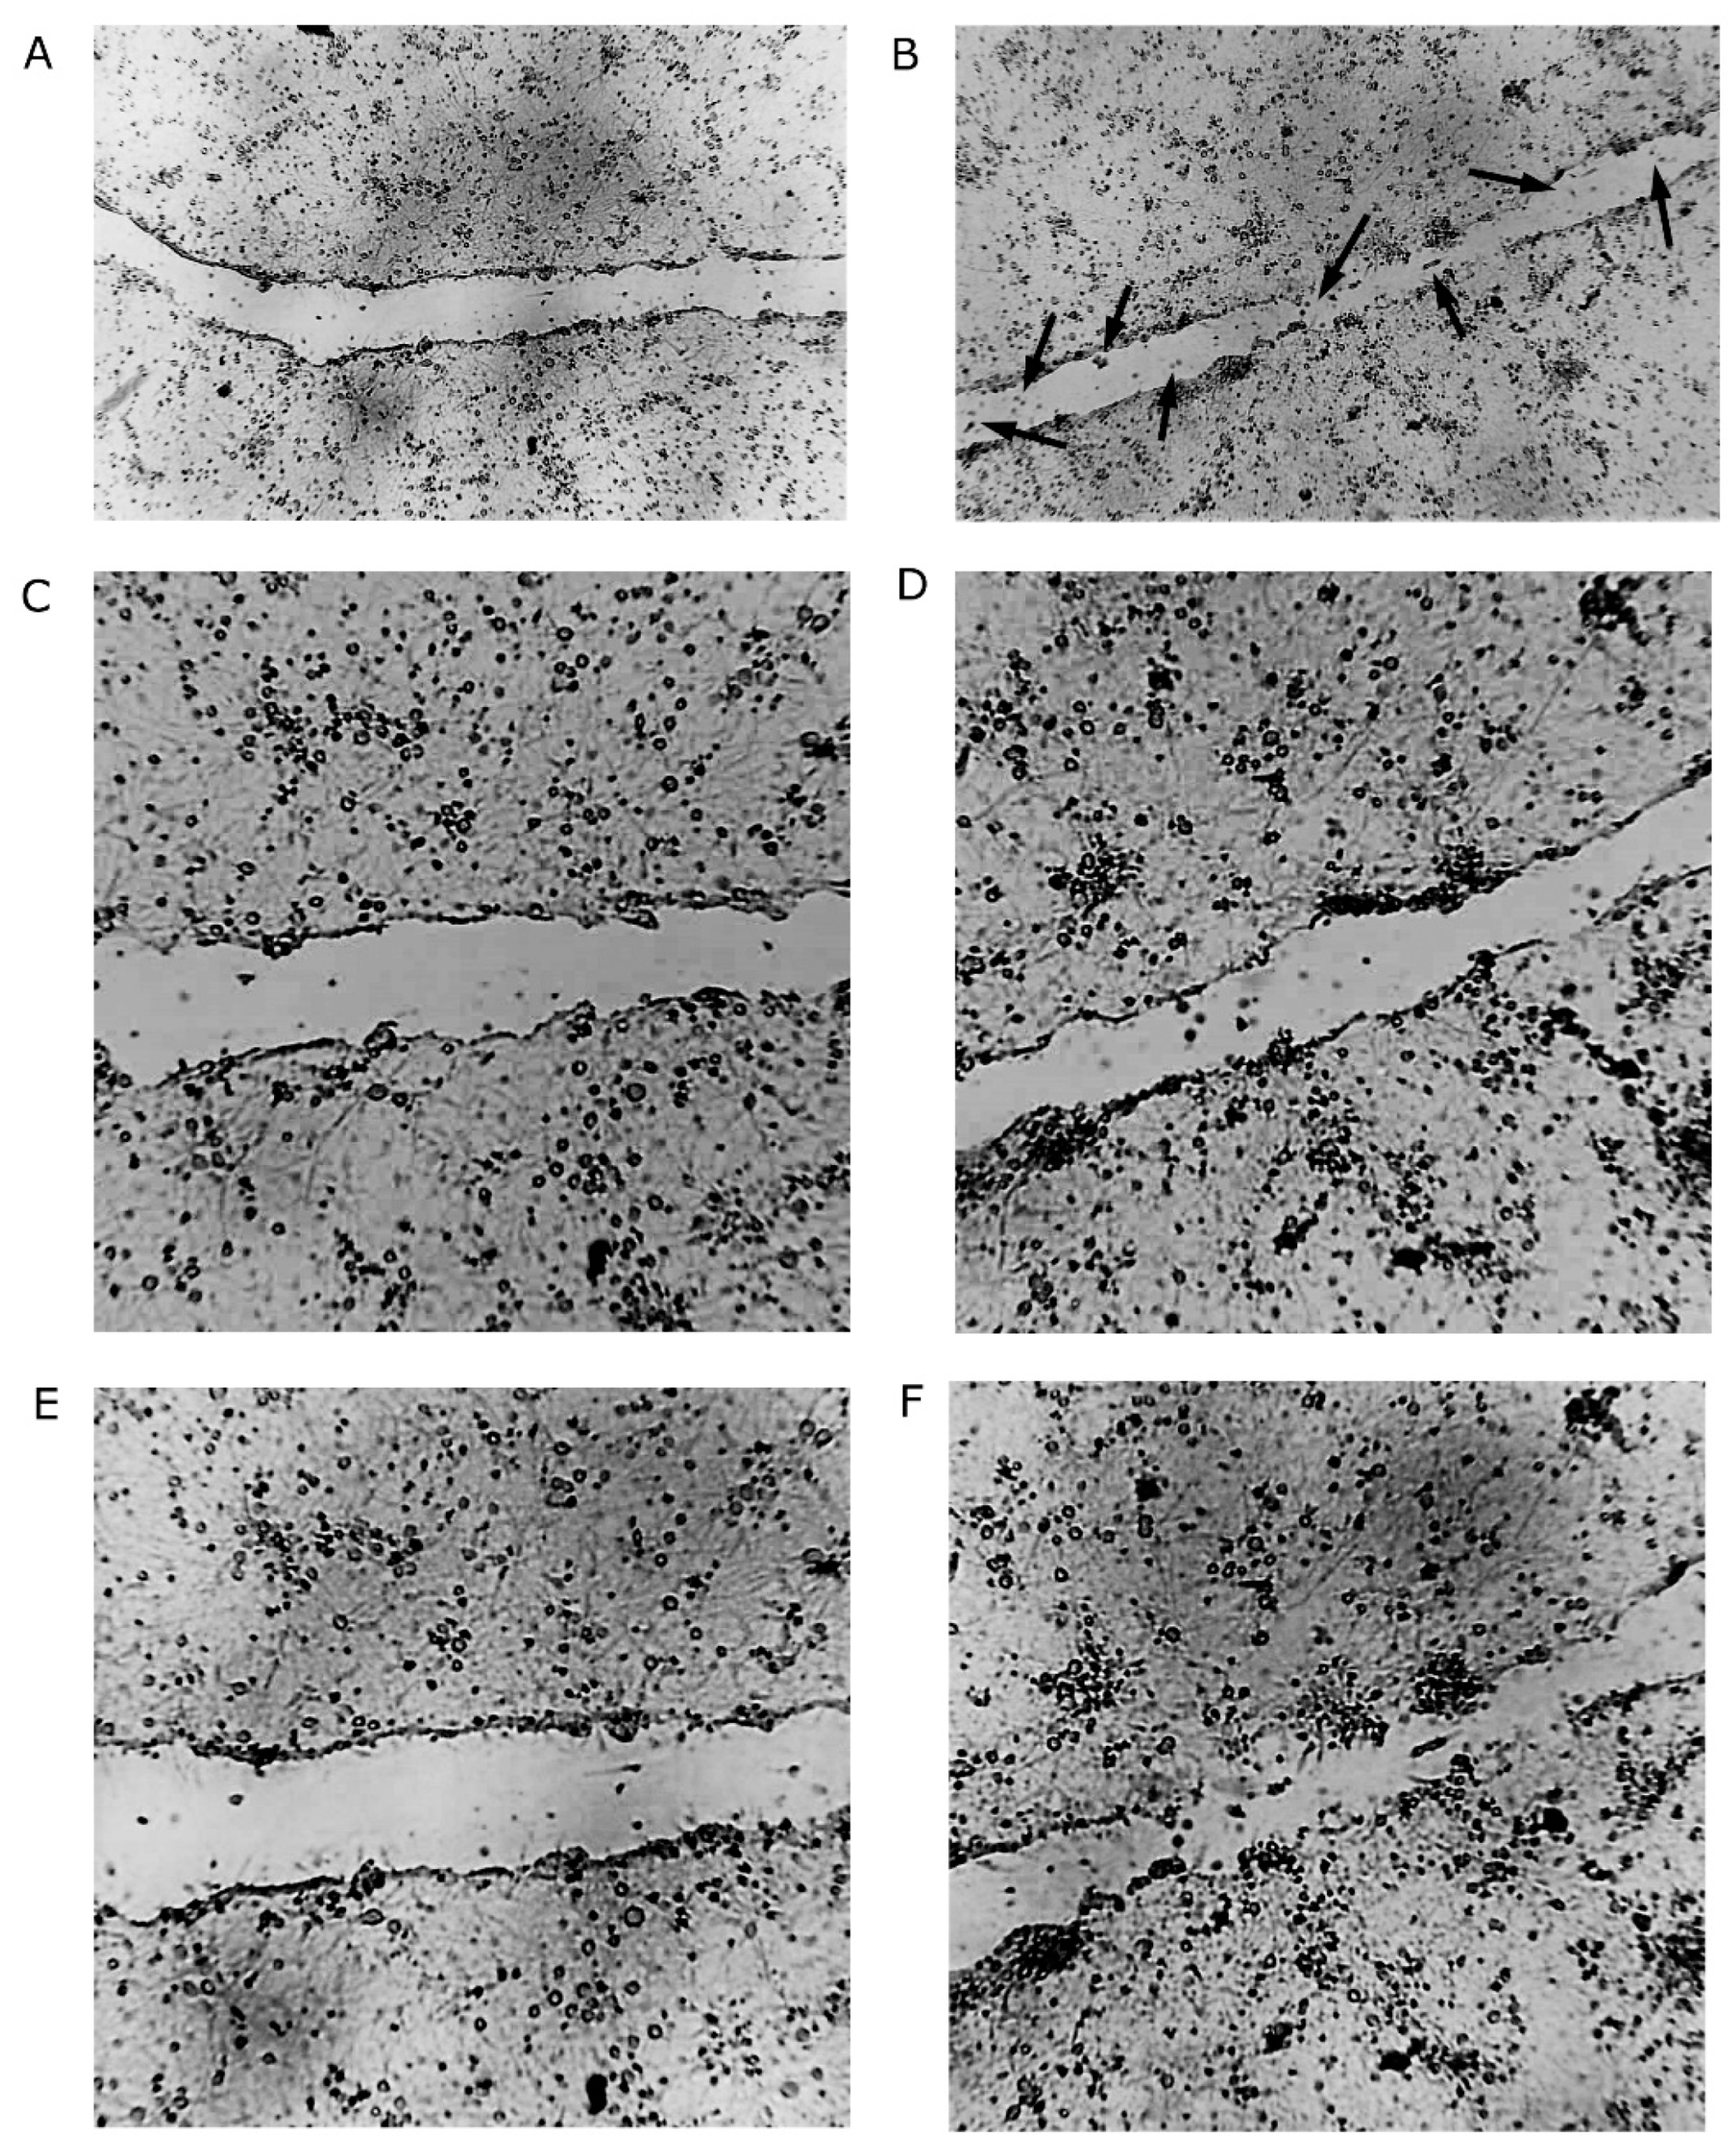

2.1. Increased Density of Cell Nuclei and Enhanced Cell Migration with BHB Treatment

2.2. Increased Synapsin and Tubulin Staining in BHB-Treated Cultures